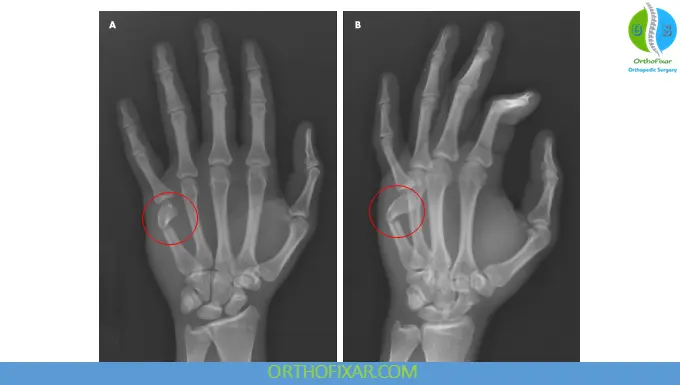

2. Imaging

- Plain X-rays (AP, lateral, oblique views) confirm diagnosis

- Assess:

- Angulation

- Displacement

- Intra-articular involvement